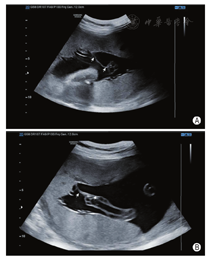

孕妇38岁,孕1产0,既往体健,无家族史及个人病史,无近亲结婚史。孕早期超声检查、孕23周系统超声检查胎儿结构均未见异常。孕30+4周超声检查:脐动脉收缩期峰值流速(Vs)与舒张末期血流流速(Vd)比值(S/D)4.0,搏动指数(PI)1.42,阻力指数(RI)0.64;偶测及脐动脉舒张期血流消失。孕31+2周超声检查:脐动脉S/D 4.83,PI 1.79,RI 0.79。孕31+5周超声检查示脐动脉舒张期血流消失。孕32+4周超声检查:脐带胎盘插入处可见纤细隔样回声,长5.4 cm,一端与胎盘子面相连,一端与脐带相连,与脐带关系密切,扫查期间内未见两者分离(图1A,图1B)。脐动脉均可测及血流信号,其一内径0.45 cm,收缩期峰值流速(PSV)30.08 cm/s,S/D 8.75,PI 1.88,RI 0.89(图2A);其二内径0.25 cm,舒张期血流消失(图2B)。胎儿大脑中动脉PSV 29.65 cm/s,S/D 4.60,PI 1.60,RI 0.78。超声提示:脐动脉血流异常,脐带根部羊膜带回声,不除外与脐带粘连。孕33+1周行剖宫产证实羊膜带缠绕脐带根部,脐带受压(图3)。新生儿1 min Apgar评分9分(肌张力-1分),5 min、10 min Apgar评分均为10分。